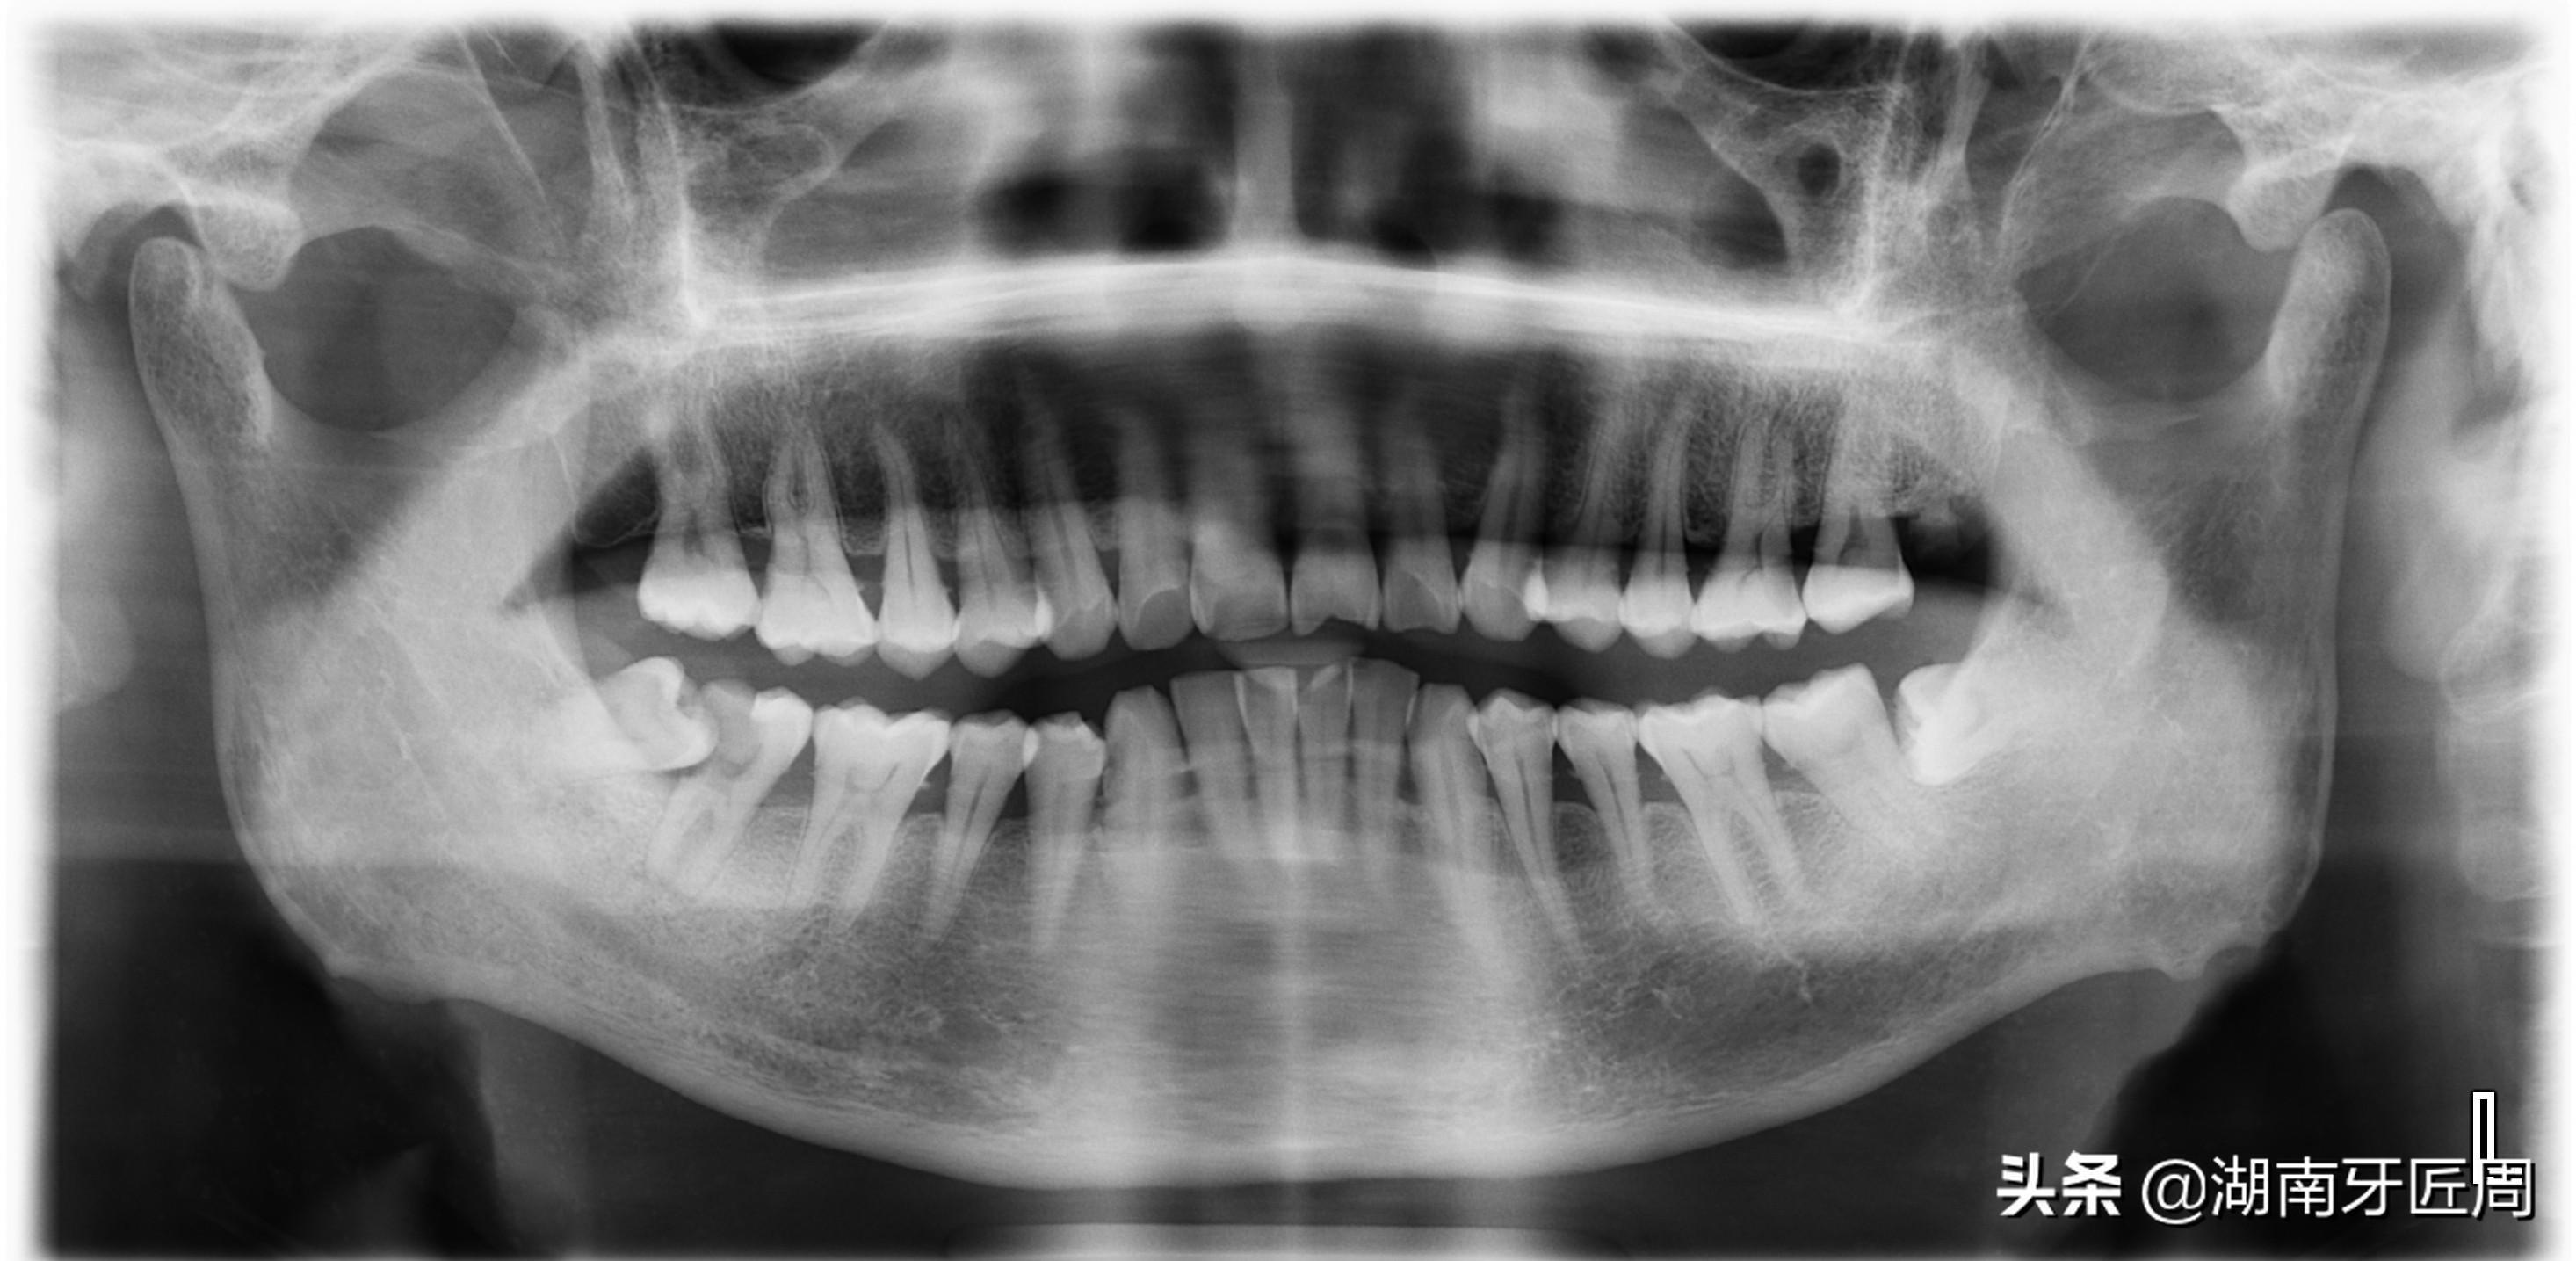

图片4.右侧智齿水平阻生,你能知道我的存在?

图片5.左侧智齿埋伏水平阻生

图片6.右侧上颌智齿接近水平阻生